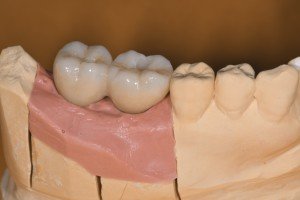

右下に埋入したストローマンインプラントの補綴です。

6番部位の埋入深度が深くなっていますが、インターナルコネクションのアバットメントなので印象操作に困難は生じませんし、スクリューリテインの補綴物なのでセメント除去の困難もありません。

フルジルコニアなので、破折の問題も回避できて、従来のアバットメント装着→補綴物作成→セメンティングの操作で生じるテクニカルエラーのリスクがほとんどありません。